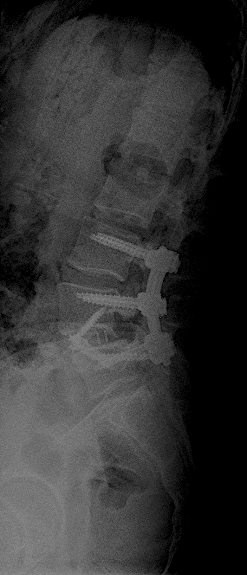

RX 6 meses